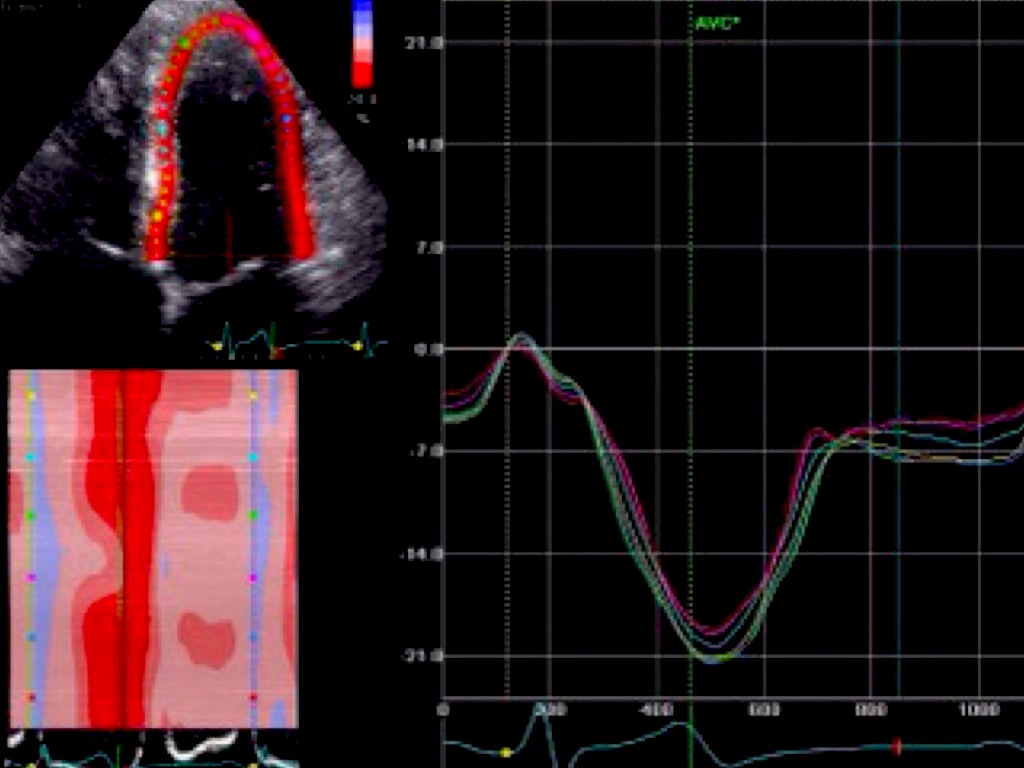

Analise objetiva da deformação miocardica

Deteção precoce alterações contratilidade segmentar

Correlação com exames funcionais já estabelecidos na Cardiologia